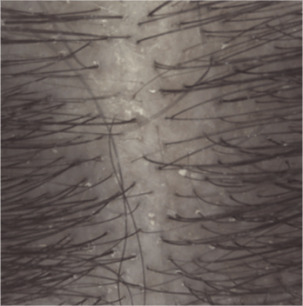

Lo shampoo KERTYOL PSO è specialmente indicato per la cura del cuoio capelluto soggetto a psoriasi.

La sua formula innovativa agisce a tutti i livelli della fisiopatologia della psoriasi. Lo shampoo trattante può essere utilizzato in associazione a trattamenti dermatologici specifici, in alternanza o come mantenimento per limitare la ricomparsa delle placche.

Risultati di efficacia

Spessore delle placche dopo 1 mese (3)